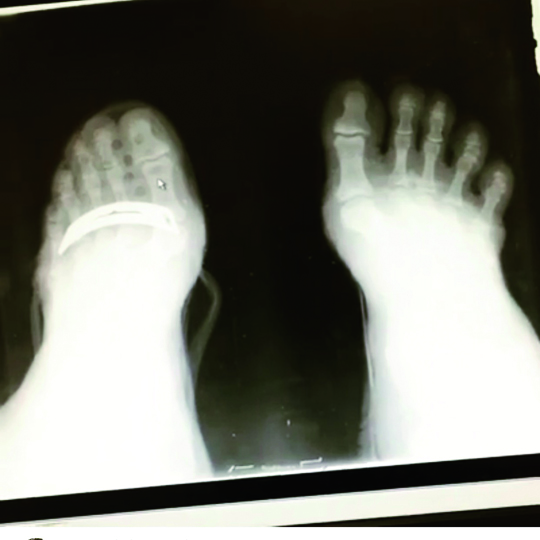

Le ossa del piede si articolano tra loro e sono fatte per potersi conformare alle rocce, alla sabbia, ai rami, tuttavia si possono riconoscere, nel piede dell’umano, delle caratteristiche della eredità arborea che ne facevano originariamente un organo da presa.

Tutti i cambiamenti che notiamo tra il piede dei nostri progenitori e il piede umano hanno come unica finalità quella di consentire una camminata più efficiente. La cosa affascinante è che umani e scimmie possiedono le stesse ossa nel piede!

Lo sviluppo più longitudinale che trasversale della struttura del piede umano ha come risultato più importante quello di riuscire a farci utilizzare il primo dito, l’alluce, in maniera molto diversa. Abbiamo mutato la sua opponibilità, fondamentale per la presa, con la sua capacità di mettere in tensione un elastico, la fascia plantare, che ci regala energia gratis ad ogni passo. La rigidità che il piede riesce a creare nella fase propulsiva del passo rappresenta la leva rigida che serve, a poter mettere in tensione le fasce, come fosse un arco.

È stato vantaggioso indossare le scarpe, per molte ragioni: per proteggere i piedi, per andare più veloce, per vanità, tuttavia il contraltare è stato non solo un impoverimento delle sensazioni ma anche una costrizione del piede, fasciato da cuoio o tela, che gli ha impedito di allargarsi, di conformarsi al terreno. Tutto questo ha irrigidito le strutture legamentose, bloccato la sensibilità dei recettori e ci ha portato una serie di disfunzioni e patologie come le fasciti plantari, le tendiniti, le fratture da stress.